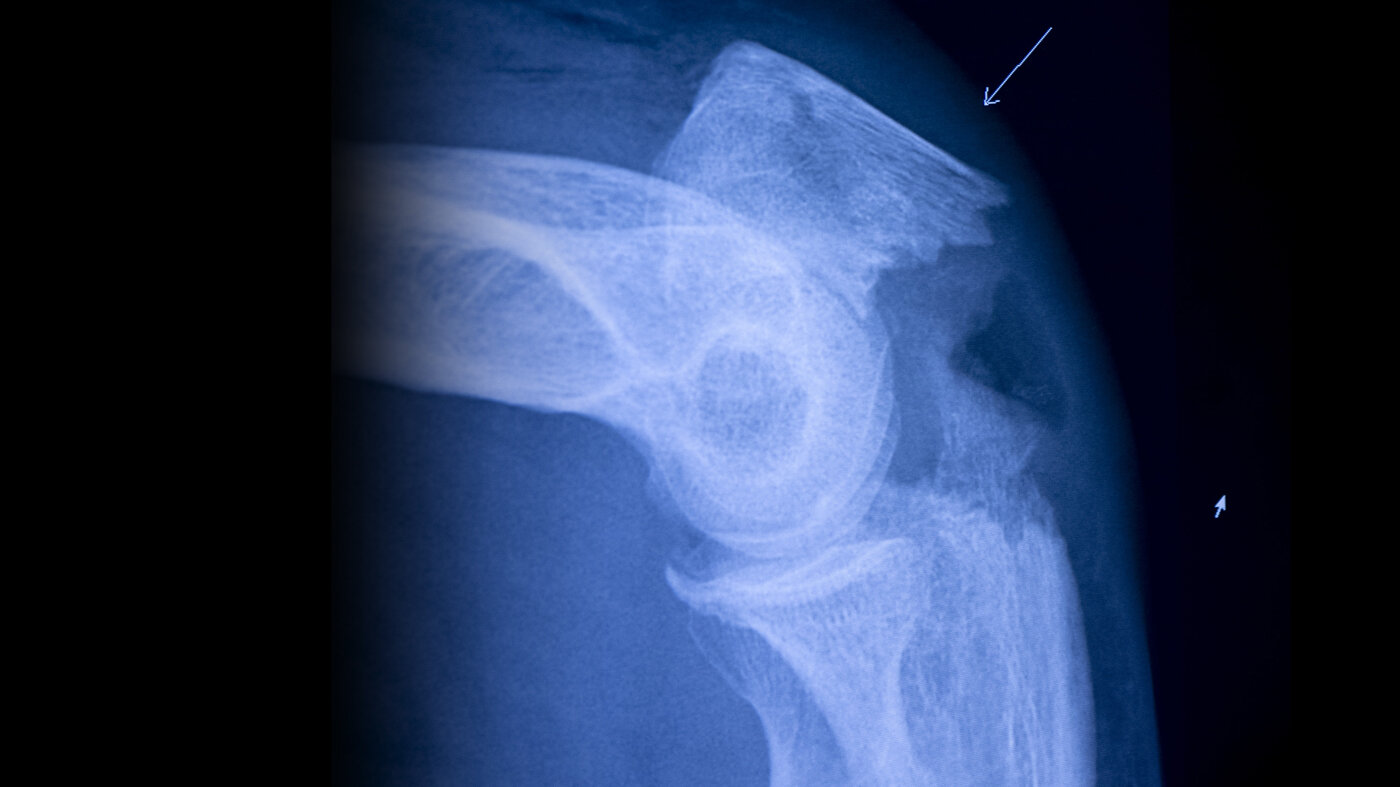

Fall koster samfunnet enorme summer i form av innleggelser og rehabiliteringstiltak. Det er et pengesluk uten like. Fall er som regel ikke en enkelthendelse, men starten på et alvorlig pasientforløp i akselererende tempo.

Fall fører til immobilitet og forverret allmenntilstand, som igjen kan føre til flere fall eller andre alvorlige komplikasjoner. Kostnadsmessig er det som en snøball som begynner å rulle, og som vokser i omfang for hver omdreining.

Men først og fremst betyr fall betydelig nedsatt livskvalitet hos eldre og risiko for en hurtig nedadgående spiral med tanke på kommende helseutfordringer.

Det vi derimot kan, er å øke bevisstheten om hvor skjellsettende et enkelt fall kan være. For et fall er ikke bare et uhell. For mange eldre pasienter kan det være starten på en katastrofe. Kan sykepleiere være med på å avverge eller utsette det første fallet, eller det andre, er det verdt mer enn summen av alle lege- og sykehusbesøkene til sammen.